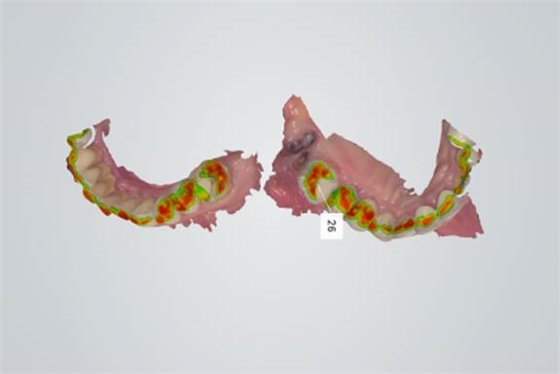

640.webp (4).jpg

5.掃描效果如圖

640.jpg

6.檢查模型的倒凹情況和咬合空間是否充足